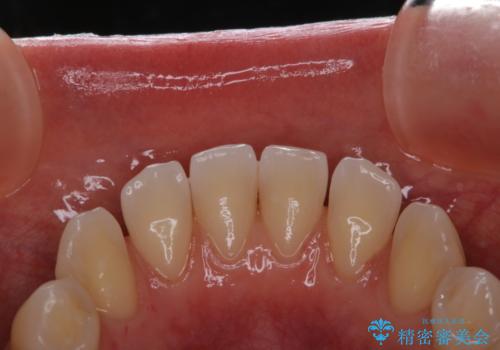

- これから矯正治療を始めていくため、きれいにしたいとのことでした。PMTC30分コースを行いました。

一見きれいに見える歯でも、染め出し(歯垢染色液)を使うとこのように歯と歯茎の境目や、歯と歯の間などに磨き残しがあることがわかります。歯磨きには、いつも気をつけているから磨き残しはナシと思っていても、実際完璧に磨ききることはなかなか難しいです。歯科医院にて、専門の機械で定期的なPMTCを行うことが大切です。